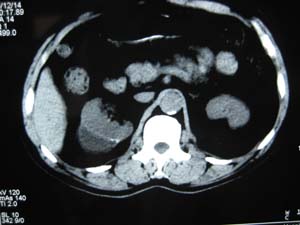

标题: CT17067:男,50Y右上腹痛一个月,无外伤史 [打印本页]

标题: CT17067:男,50Y右上腹痛一个月,无外伤史

右肾包膜下积液,包膜可见线状钙化

不除外慢性血肿

右肾包膜下积液(陈旧性血肿?),包膜可见线状钙化。

右肾包膜下积液,包膜可见线状钙化。左肾可疑血管平滑肌脂肪瘤,把窗调宽一些.